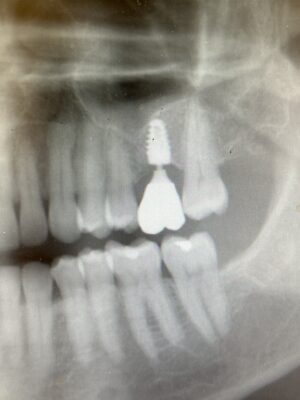

I have a non-implant case that im having issues with pt management so i thought id ask y’all what to do. I did bridge for pt from 18-20 and ext #19 in 2020. I saw her feb 10 2023 b/c she claims that the ext of 19 hurts and her other dentist stated i left a root. Im going to also include a pano i captured after ext showing how small the piece i…